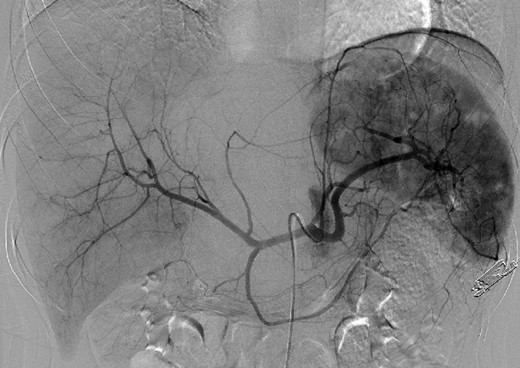

An 18-year-old woman presented with epigastric pain that started during a Japanese drum lesson. She was diagnosed with rupture of a hepatic tumor and transported to our hospital. She had no medical history of surgery, including abdominal surgery. Contrast-enhanced computed tomography (CT) revealed a 13-cm, low-density giant mass in the left hepatic lobe and high-density ascites, indicating abdominal bleeding from the liver tumor (Fig. 1). Ultrasonography confirmed a well-defined giant mass of the liver, comprising both cystic and solid lesions. Laboratory data showed a low hemoglobin level of 8.2 g/dl, and all the results of liver function tests and tumor marker measurement were within normal ranges. The patient underwent emergent celiac angiography, which revealed an avascular tumor with no evidence of extravasation from the hepatic artery. The left hepatic artery was considered to be the artery feeding the tumor and was embolized (Fig. 2). Magnetic resonance imaging (MRI) confirmed a well-defined giant multilocular lesion with fibrous partition (Fig. 3). After the patient's condition stabilized, she underwent left hepatic lobectomy. Laparotomy revealed bloody ascites and a large tumor in the left lobe of the liver; the right lobe appeared normal. The enlarged lymph nodes of the hepatoduodenal ligament were also dissected. Histological analysis of the resected specimen revealed a huge cystic mass of ∼12 × 9.5 cm. The mass was cystic and multilocular with a fibrous wall and filled with a massive blood clot (Fig. 4). The enlarged lymph node had a 25 × 23-mm cyst, which contained yellowish fluid. On microscopic examination, the wall of the cyst consisted of a tight elastic fiber meshwork composed of collagen fibers, which was accompanied by a small amount of acid mucopolysaccharide in the stroma and a lining of single-layered flat cells on the inner wall (Fig. 5a and b). Immunohistochemical staining revealed that the cyst wall was positive for both the endothelial marker CD31 and the lymphangial marker D2-40 (Fig. 5c and d). The cystic structure of the lymph node also was composed of elastic fiber components similar to those of the cyst in the liver and lined with single-layered flat cells, which were immunohistochemically positive both for CD31 and D2-40 (Fig. 5e). The pathological diagnosis was hepatic lymphangioma combined with lymphangioma of the lymph nodes. The patient's postoperative course was uneventful, and she was discharged on Day 8. During follow-up for almost 4 years since the surgical treatment, the patient has presented no sign of recurrence.

Emergent angiography demonstrated an avascular tumor and did not reveal any extravasation from the hepatic artery.